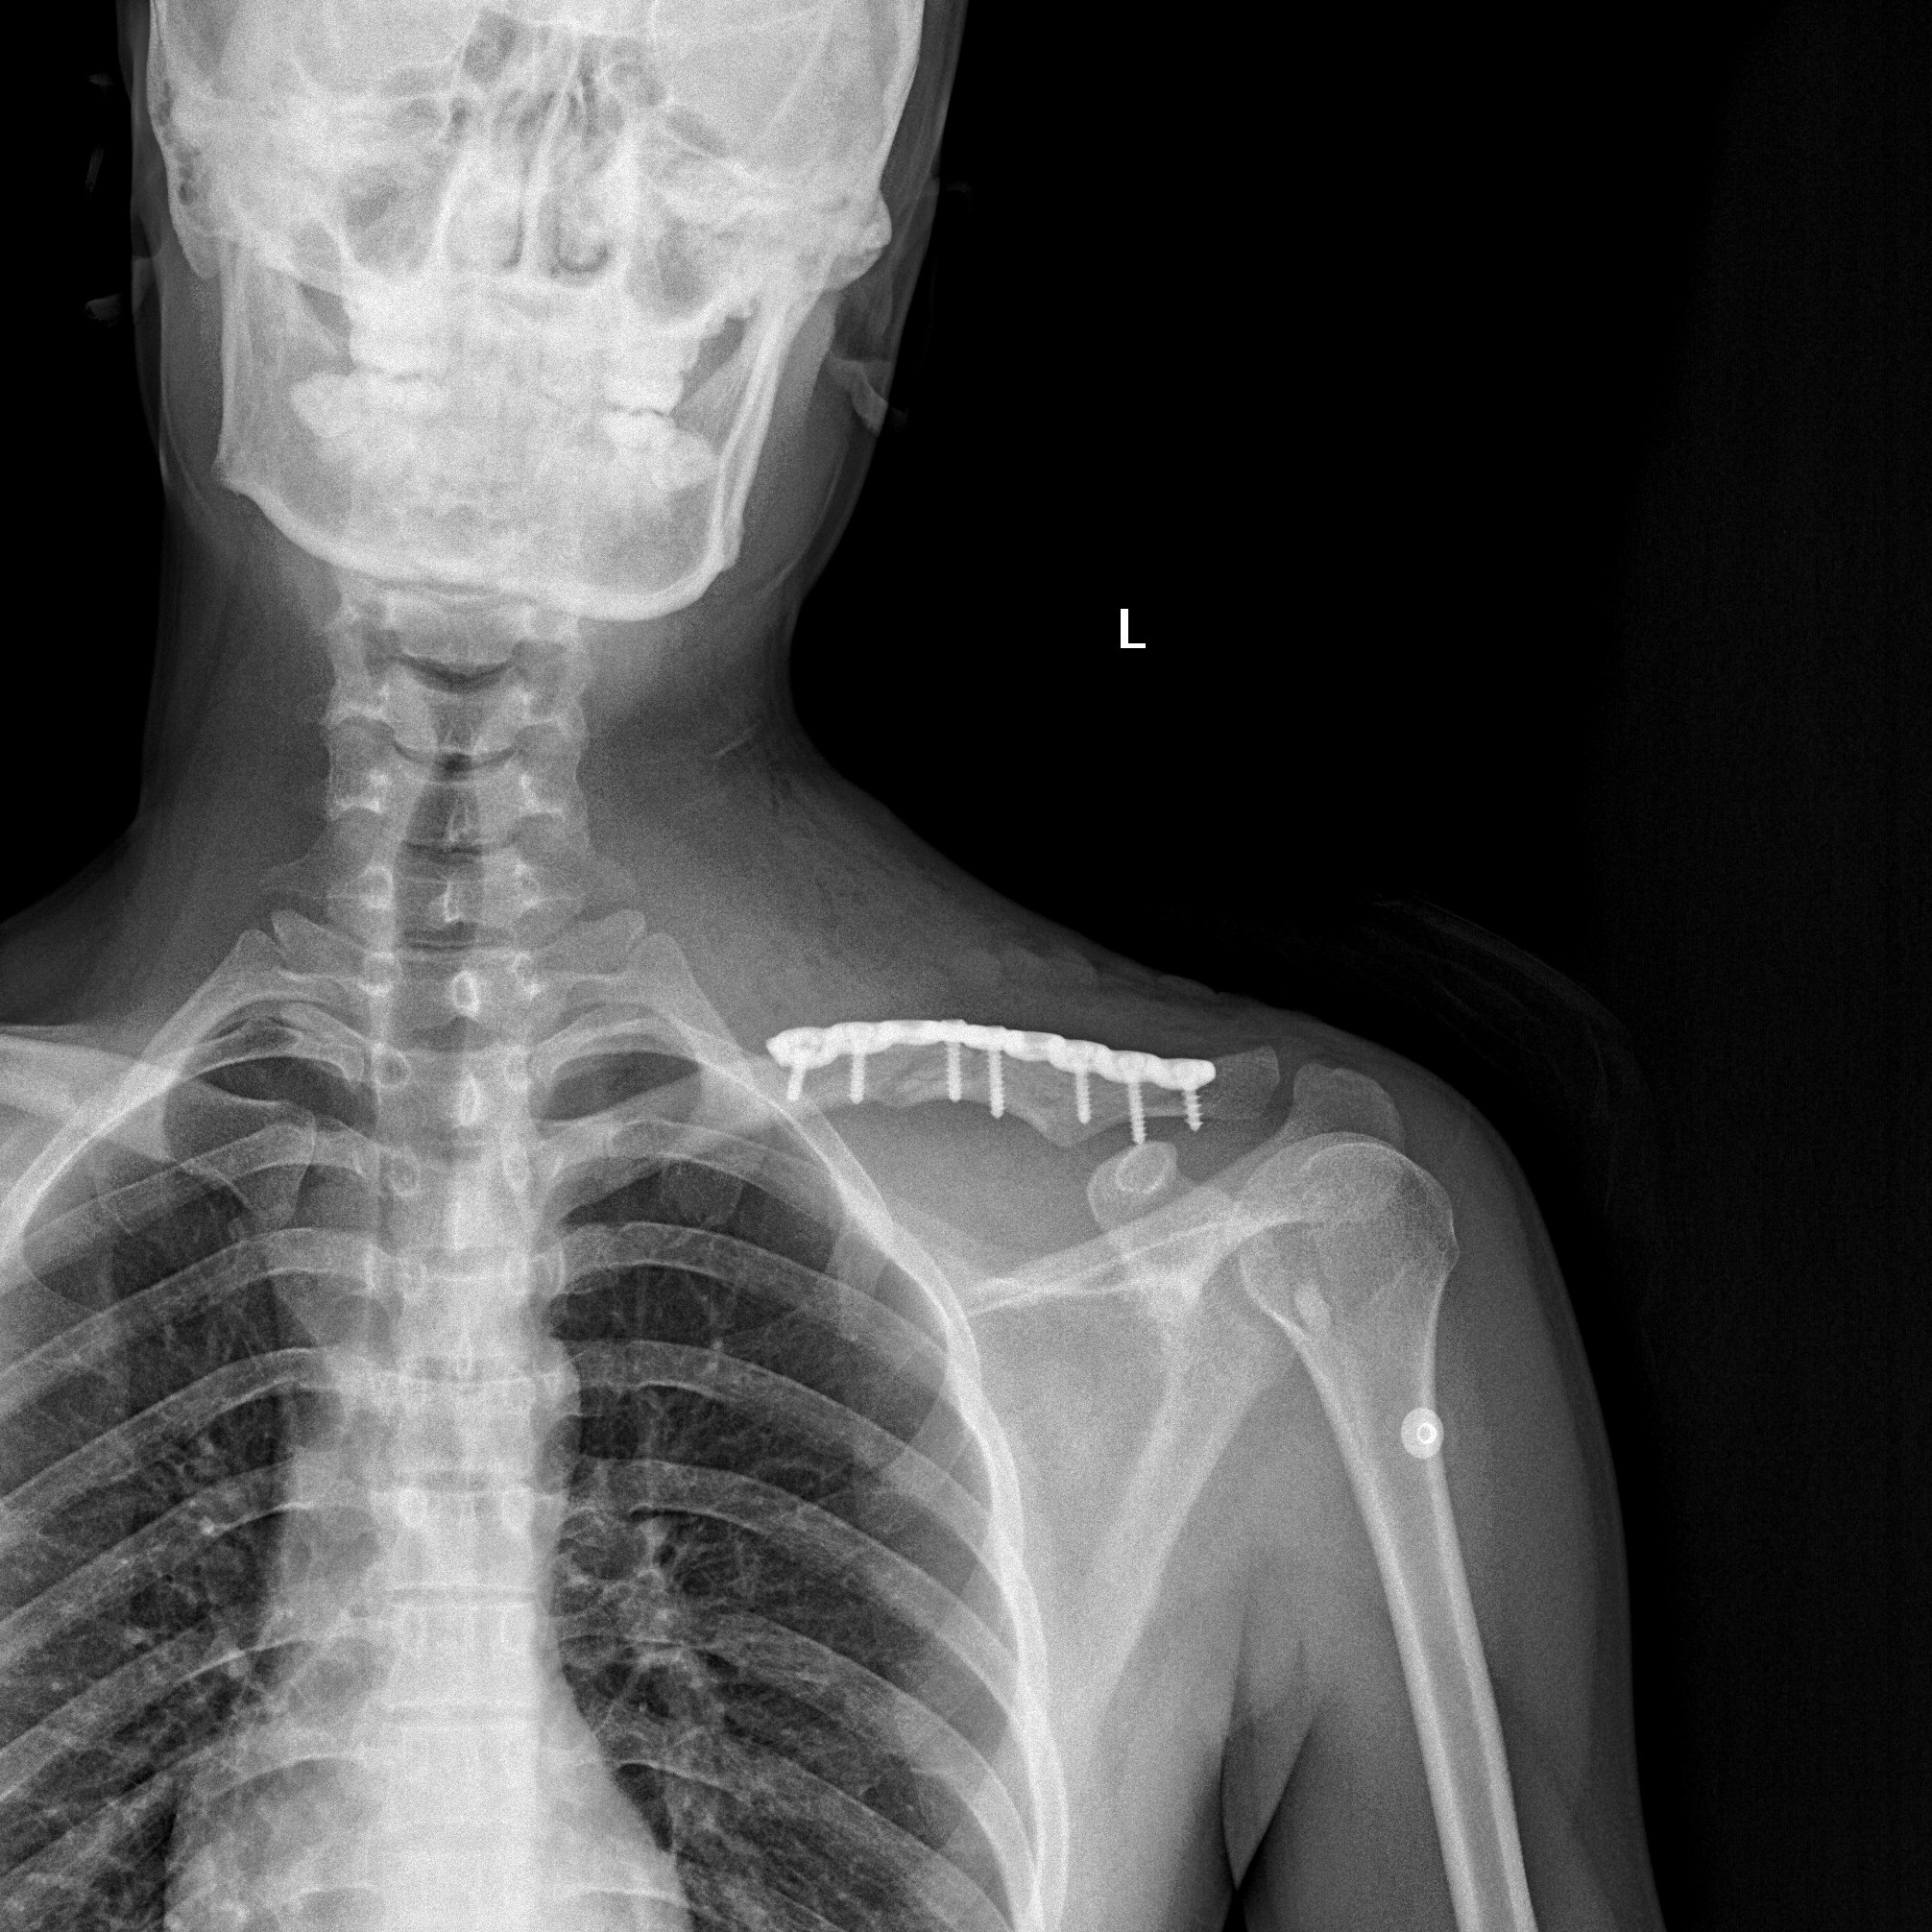

锁骨远端骨折

锁骨远端粉碎骨折

锁骨骨折手术前后